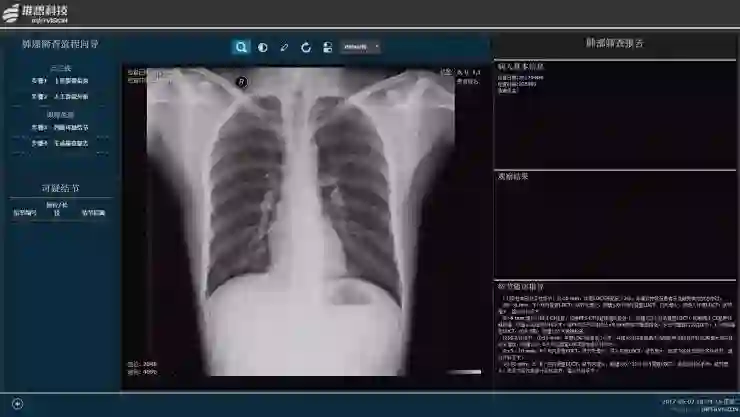

智能 X 线辅助筛查产品(AI-DR)

由于成本较低,X 线始终是基层医院筛查的第一手段,但就目前来看,影响力在降低,很多病兆,通过 X 线不容易看出来,特别像磨玻璃结节。但是,在通过人工智能技术增强后,很多原来人眼分辨不出来的东西,机器能分辨出来。

推想科技的智能 X 线辅助筛查产品能够对心胸部位的20多种不同病灶进行判断,既可以帮助体检医生迅速筛检出存在病灶的影像,又可以在门诊住院病例的诊断过程中迅速标识出病变位置。尤其在肺结节检测上,表现突出,在合作医院试用过程中检测出数例险些被遗漏的肺癌病例,为放射影像诊断的质量提供了保障。

陈宽预测,很多人一开始觉得 X 线会被淘汰,但在结合了人工智能技术之后,它的作用和价值还是无可替代的。